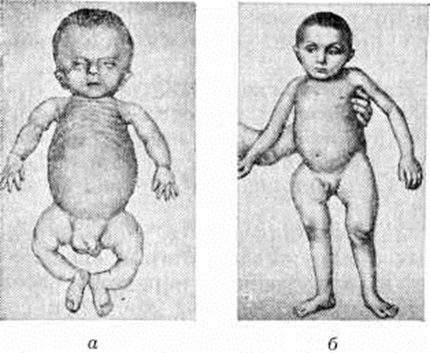

При врождённом Остеогенез несовершенный дети рождаются слабыми, часто нежизнеспособными. Кожа тонкая, бледная, подкожная клетчатка истончена. Характерна общая гипотония, переломы, возникшие внутриутробно или во время родов. Переломы чаще обнаруживаются в области диафизов бедренной кости, костей голени, плечевой кости и костей предплечья, реже грудины, ключицы, и тел позвонков. Мягкие и податливые кости головы плохо защищают головной мозг во время родов.

При позднем Остеогенез несовершенный клинические, проявления менее выражены. Переломы костей характеризуются более доброкачественным течением, проявляются местной болезненностью и небольшой припухлостью. Переломы могут быть полными и неполными, обычно бывают поднадкостничными. Отломки чаще смещаются под углом, в последующем развиваются дугообразные искривления (рисунок 3). Смещение по длине и ширине наблюдается редко. Консолидация происходит быстро с образованием большой костной мозоли. Вслед за одним переломом вскоре возникает другой, рядом с ранее происшедшим. Общее число переломов может достигать от 5 до 20 и более.

Вследствие преимущественного поражения длинных трубчатых костей развивается характерная картина микромелии: конечности становятся непропорционально короткими при нормальных размерах головы и туловища. Для Остеогенез несовершенный типичны нормальные размеры кистей и стоп, фаланги никогда не ломаются, а кости пясти и плюсны — лишь в редчайших случаях. Основание черепа, позвоночник и грудина при Остеогенез несовершенный не ломаются. К периоду полового созревания ломкость костей обычно значительно снижается.